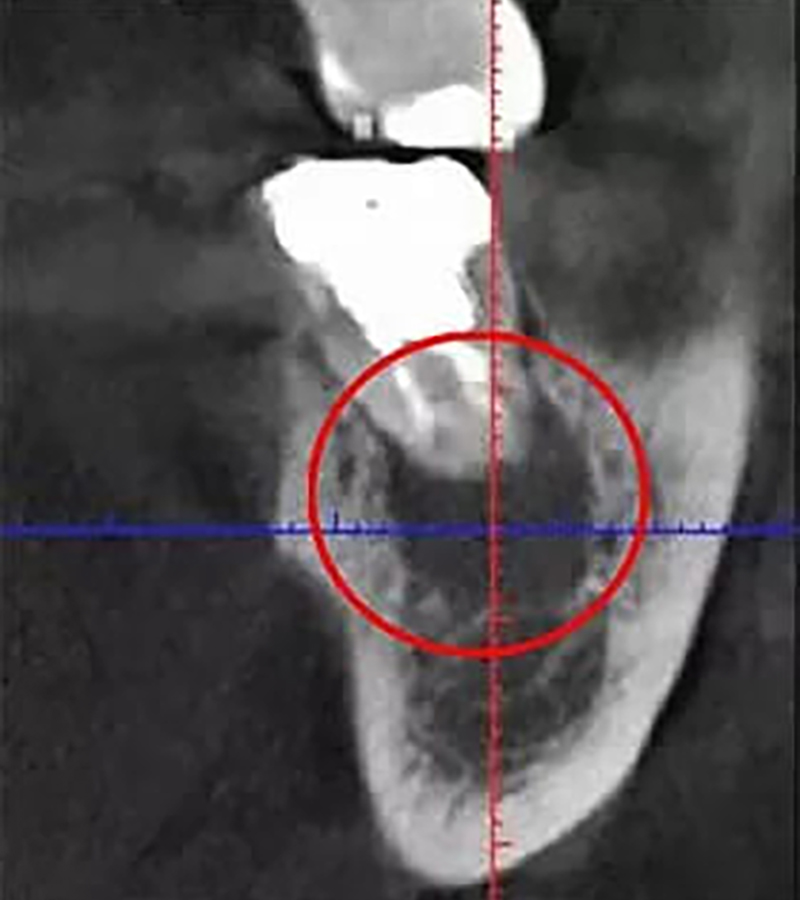

一般的なレントゲンは2次元(平面)の画像しか撮影できませんが、CT装置は顎の状態を3次元(立体)で撮影することができます。CT装置を使うことで診断の精度が大幅に向上し、レントゲンでは確認できなかった部分まで詳しく見ることができるのが大きな強みです。

以下は、CT画像とレントゲン画像です。このように、レントゲンだけでは病巣を見つけられなかった可能性があります。「見つからない=治療ができない」ということになり、それは根管治療の再発リスクが高まることを意味します。

• CT画像

CT画像